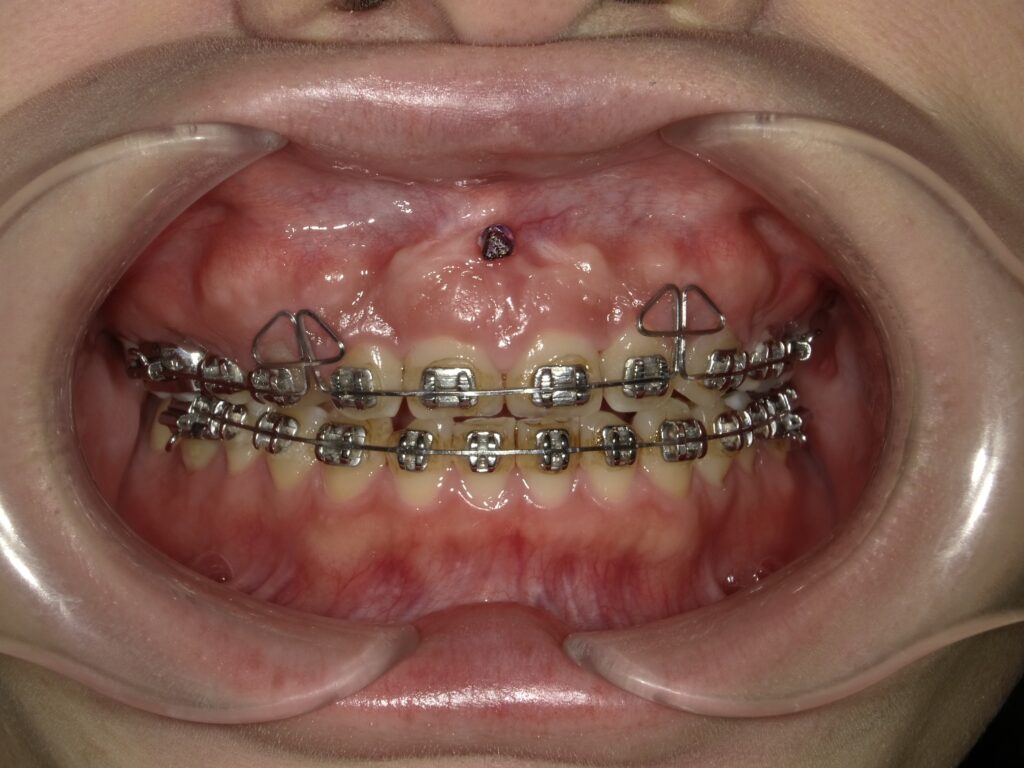

アンカースクリューとは、歯科矯正治療において使用される小型のチタン製のネジです。直径は約1〜2mm、長さは6〜10mm程度で、口腔内の骨に一時的に埋め込まれます。写真では、上顎の真ん中に打ちこまれています。